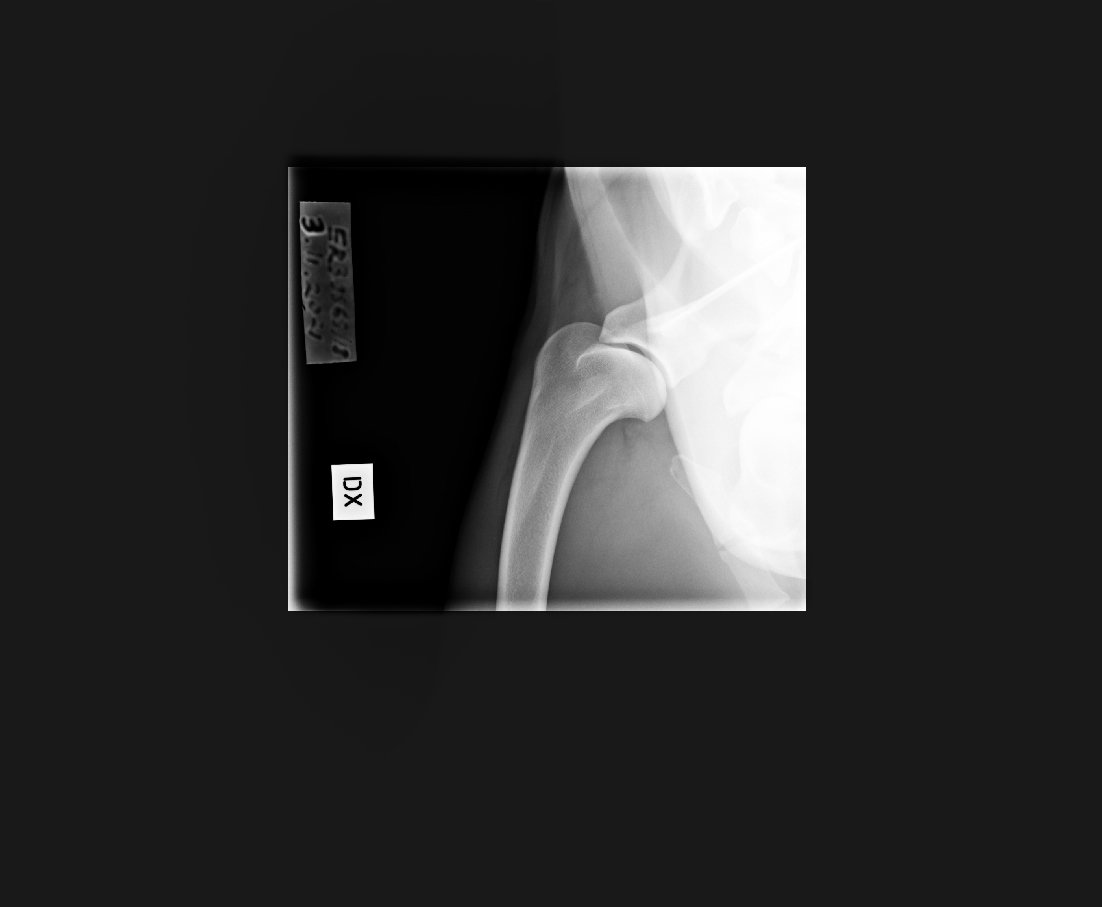

Kyynärpäät

0/1

Olkapäät (11/21):

vasen terve,

oikea tulkinnanvarainen